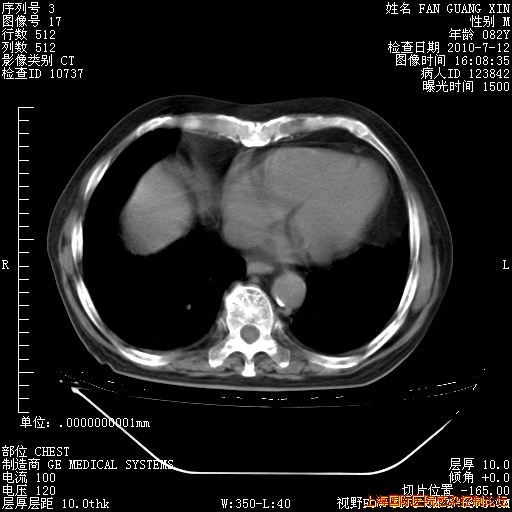

今天CT

整整相隔30天的肺部CT好像有所好转啊。甲强龙减量第3天,需要观察体温。

海管,自昨日你和我通完话后,不知您岳父消化道症状有无缓解?体温怎样?阅读7.12日胸部ct,个人认为目前激素治疗是有效的,甲强龙减量是适宜的。因在抗痨治疗,需密切观察肝功、肾功能和血常规。不过,老年、长期住院和大量使用激素,很担心菌群失调发生